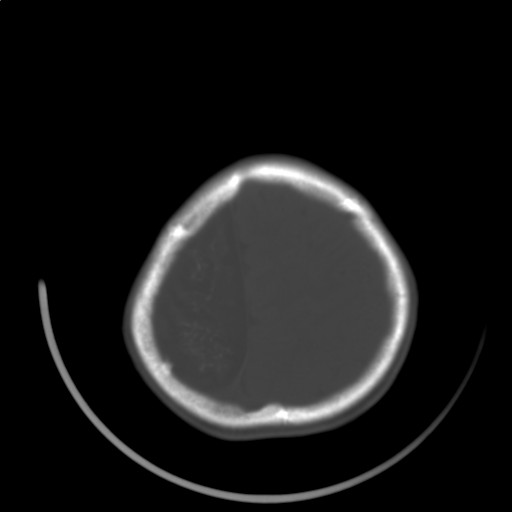

标题: PED3416:F,12Y,智力下降,学习成绩差,8个月时发过高烧。

右侧半球萎缩,软化,多量脑回样钙化,考虑颅面血管瘤病,建议dsa检查

右侧半球萎缩,软化,多量脑回样钙化,同侧颅盖板障增宽,考虑颅面血管瘤病,建议dsa检查与化脓性脑膜炎后遗改变鉴别。